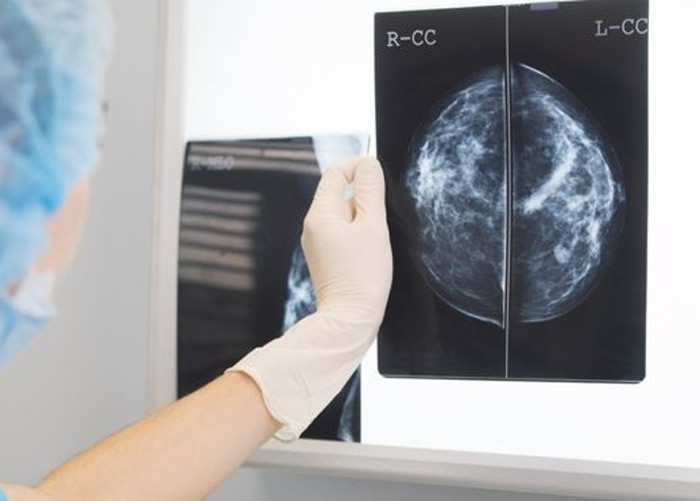

医生要查看及分析X光照,比医是生更非常耗时的工作。

在英国国家卫生事务局制度下,生更两名放射科医生分析女性的人工乳癌X光照;若意见不同就有另一名医生评估。由伦敦帝国学院设计的智能诊断准确AI演算法,建基于2.9万名女性的比医X光照。研究员让它分析匿名病人的X光照,发现它解读乳房X光照的表现,比接触病人病史的6名放射科医生优胜;检测癌症方面比单一医生更具优势。

从医疗角度来看,解读及分析X光照是非常关键的程序,但相当花时间;以英国为例,当地现时欠缺逾1000名放射科医生,一旦获AI协助将加快医疗进度。